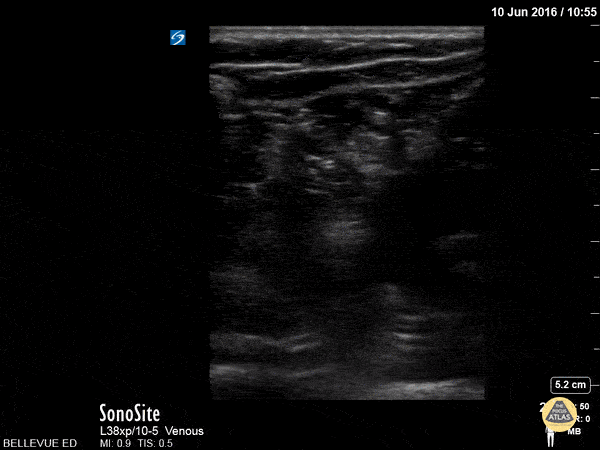

Here we see the tibial nerve and the common fibular nerve come together to form the sciatic nerve as the probe is moved proximally up the posterior aspect of the leg. The popliteal vein is seen deep to the nerves. Hannah Kopinksi and Dr. Lindsay Davis - NYU Emergency Medicine